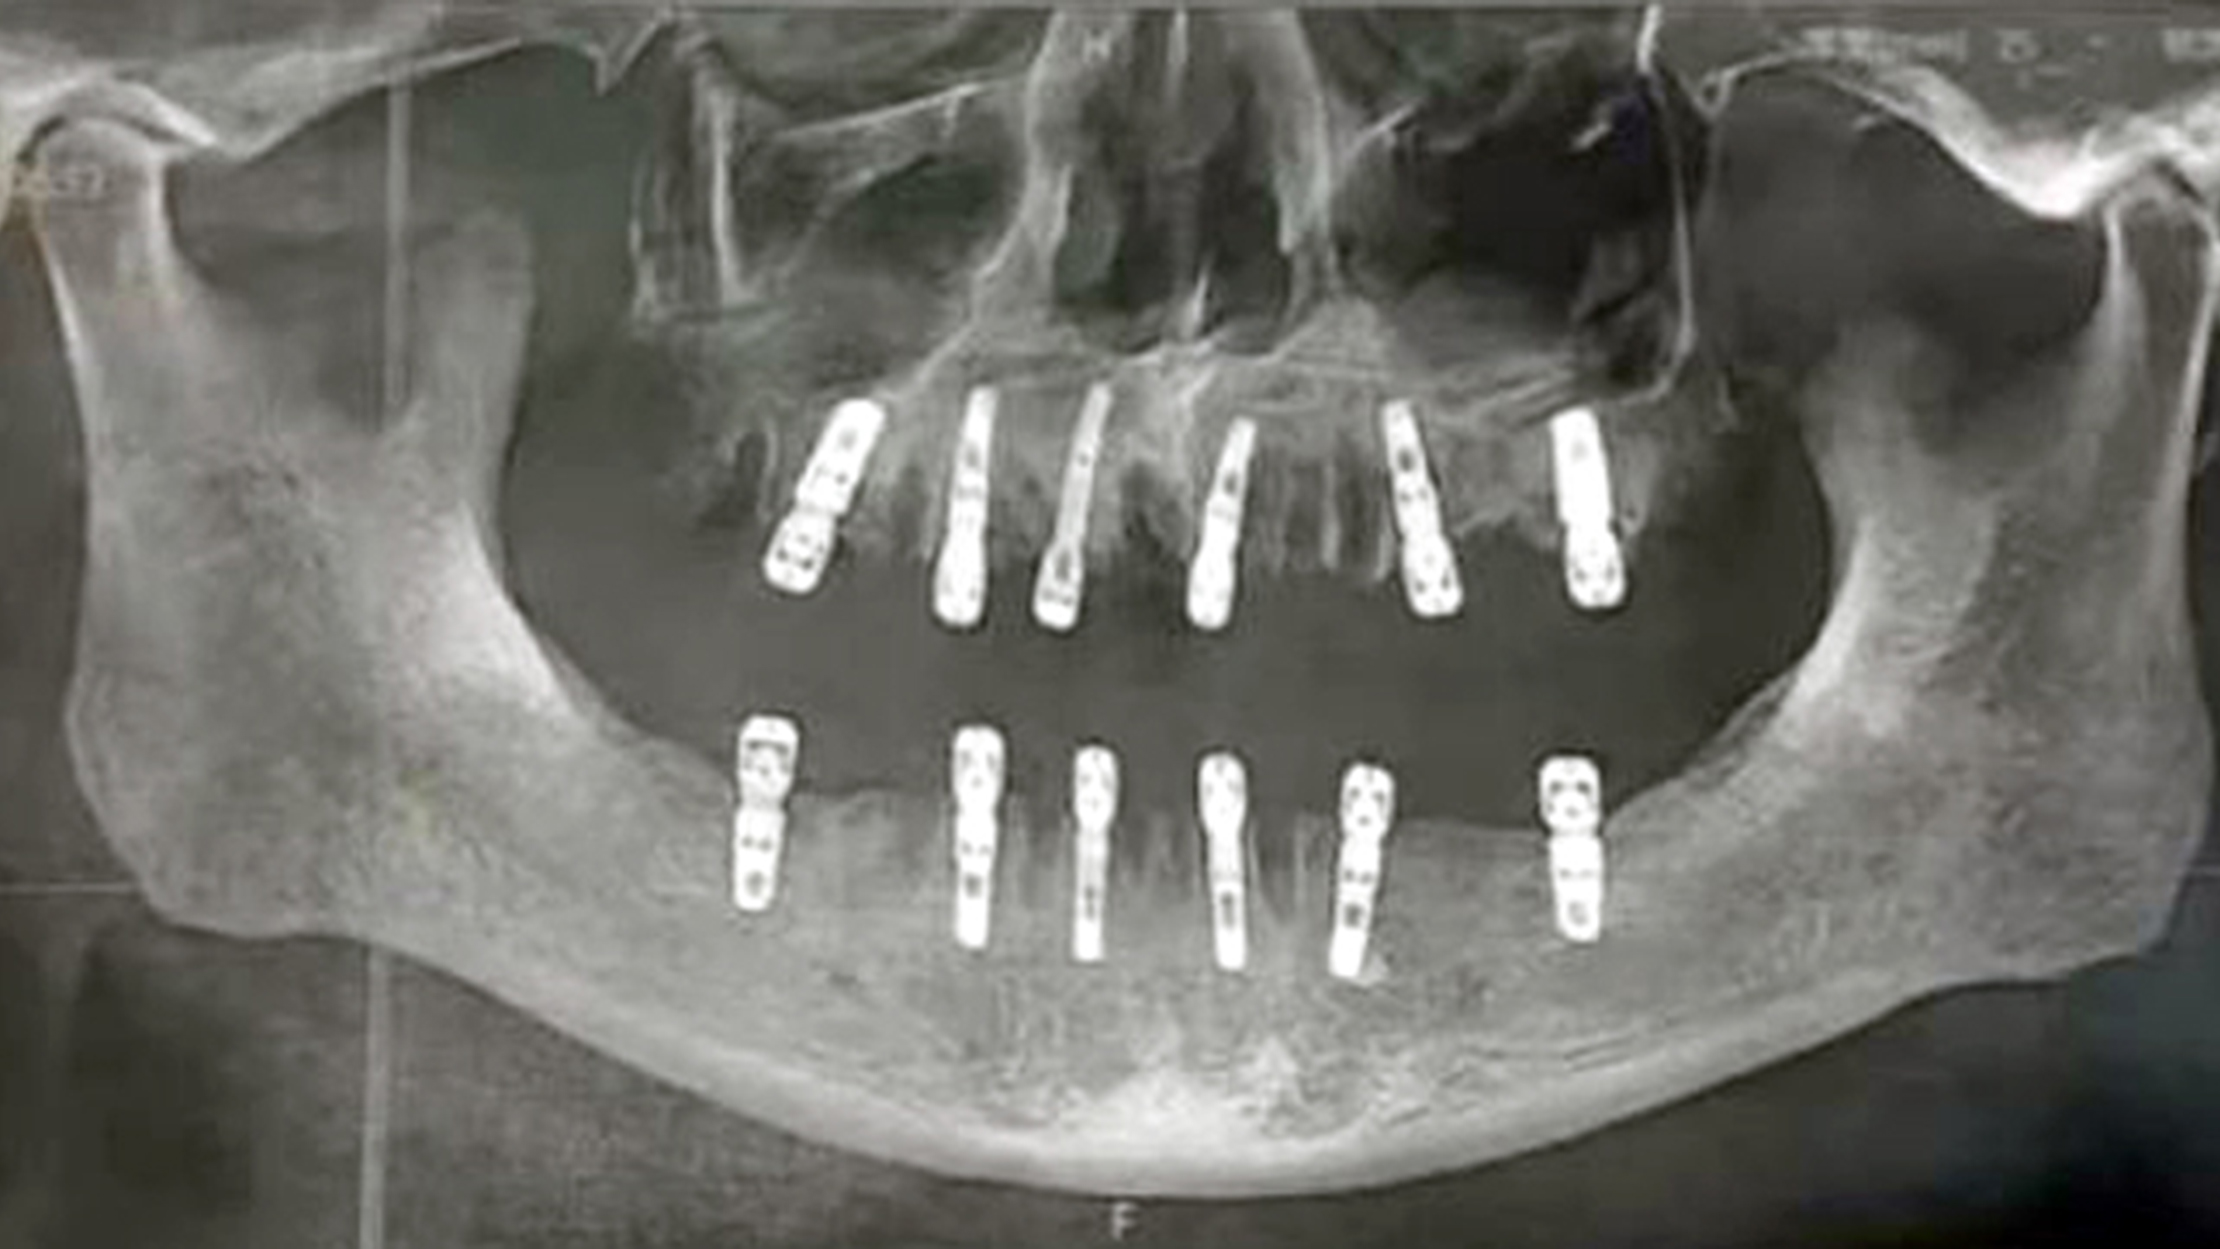

تحقِّقُ السلطاتُ الصينيةُ في حالة رجل تُوفي بعد 13 يومًا من خلع 23 سنًا وزراعة 12 غيرها في اليوم نفسه بعيادة أسنان. وتقدّمت شو، المقيمة في مدينة يونغكانغ، في مقاطعة تشجيانغ الصينية، مؤخرًا بشكوى إلى مكتب الصحة البلدية ضد عيادة أسنان محلية بعد وفاة والدها، بأدلة على أنه خلع 23 سنًا وزرع 12 أخرى في جلسة واحدة، والتي تدّعي أنها تسببت بوفاته المفاجئة بعد 13 يومًا. وأخبرت شو السلطات أن والدها عانى آلامًا مبرحة طوال الأيام الثلاثة عشر الأخيرة من حياته، قبل أن يعاني نوبة قلبية قاتلة، والآن تريد المرأة تقديم المسؤولين إلى العدالة. وقال شيانغ غولين، مدير مركز طب الفم بمستشفى ووهان الرابع: «كلما زاد عدد الأسنان التي تقوم بخلعها، زادت استجابة المريض للألم وزادت احتمالية الإصابة بالعدوى بعد الجراحة».